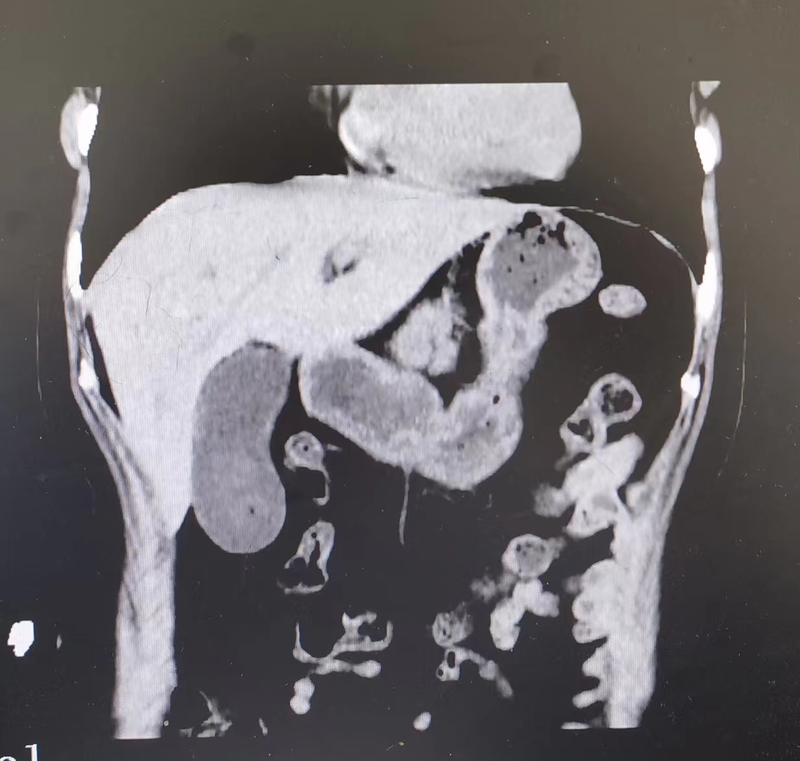

胆囊炎为常见疾病,急性发作时可引起上腹痛等症状,但一般不会引起较重的肝损伤,但我们也遇到少数急性胆囊炎或慢性胆囊炎急性发作引起严重肝损伤的情况。举1例女,53岁,右上腹部疼痛伴腰背部胀痛2天入院,询问病史,病人无服药史,无饮酒史,无肝炎病史等。急症CT查胆囊肿大伴片状结石影(图1)。入院后磁共振提示胆囊炎,胆囊结石(胆管无扩张,直径2.77mm)(图2),血生化提示转氨酶升高明显,尤其是ALT,GDH明显增高(图3),说明肝损伤严重,病人总胆汁酸正常,说明不存在胆道梗阻(虽然总胆红素有升高,应为病人肝损所致),不宜马上手术,复查后仍有升高,再复查,ALT在500U/L以下后行腹腔镜胆囊切除术,胆囊存在水肿,术后转氨酶进一步下降,顺利出院。胆囊炎发作虽然一般不会引起严重肝损伤,但也会有少数病人会出现。所以,对每一个胆囊炎发作病人都要引起重视,不要用肝损的药物,要查肝功能,及早发现和防止病情加重。